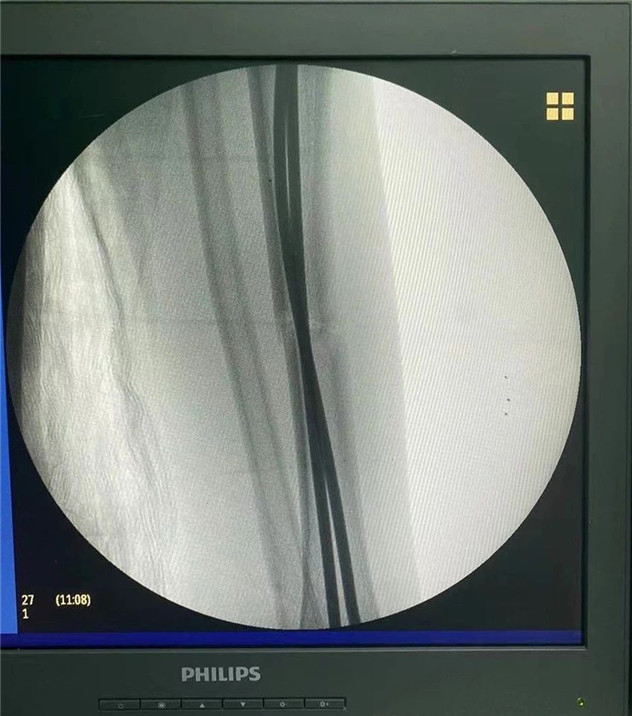

術中

2020年10月5日,在完成術前檢查后,睿睿接受了閉合復位彈性釘內(nèi)固定術,手術由羅軍主任主刀。術中只需要兩個1厘米的小切口,精準微創(chuàng),僅一個小時,手術便圓滿完成。